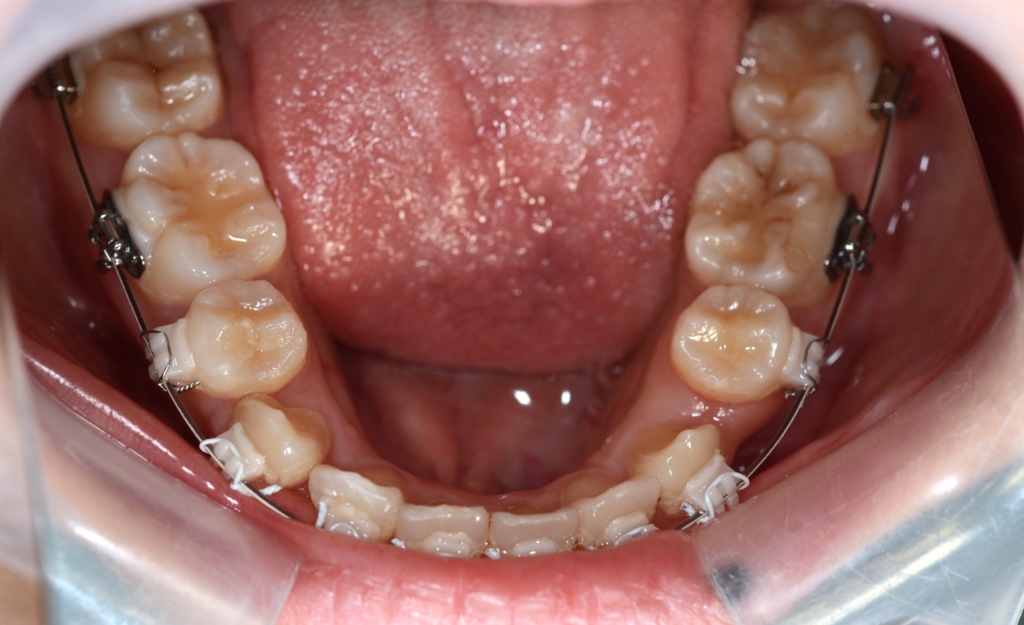

マルチブラケットシステム(ハーフリンガル type)で矯正を開始。

上下の左右の奥歯を1本ずつ計4本抜歯(4番目の第一小臼歯を抜きました)

1.上下の左右の奥歯を抜歯をしてスペースを作り、前歯をきれいに並べる

2.残る隙間分は、できるだけ前歯を奥へ引っ込める